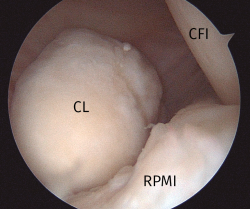

Figura 1. Imagen del compartimento posteromedial desde una visión transescotadura desde el portal anterolateral, rodilla derecha. Se evidencia la presencia de un cuerpo libre “oculto”. CFI: cóndilo femoral interno; CL: cuerpo libre; RPMI: rampa posterior de menisco interno.

La exploración transescotadura de los compartimentos posteriores puede cambiar el diagnóstico en el 18% de los casos de artroscopia de rodilla y alterar el plan terapéutico en el 11%; en casos de cirugía del LCA puede ser incluso mayor(29). Puede ayudar a diagnosticar un 45% de roturas meniscales ocultas, y un 33-36% de cuerpos libres ocultos(28,29).

Esta técnica no forma parte de los gestos habituales durante una artroscopia rutinaria de rodilla, pero resulta muy útil en cirugías como la resección de ciertos tumores (destacando por su frecuencia la sinovitis villonodular pigmentada) (Figura 7), el abordaje a la fabela (Figura 8), la extracción de cuerpos libres o el reanclaje de avulsiones óseas de la inserción tibial del LCP. Además, la creación de este portal permite una buena visualización de la porción posterosuperior de ambos cóndilos femorales y de la cara posterior del LCP, del ligamento de Wrisberg, del tendón poplíteo y de la unión meniscocapsular de ambos meniscos(24)(Figuras 9 y 10).